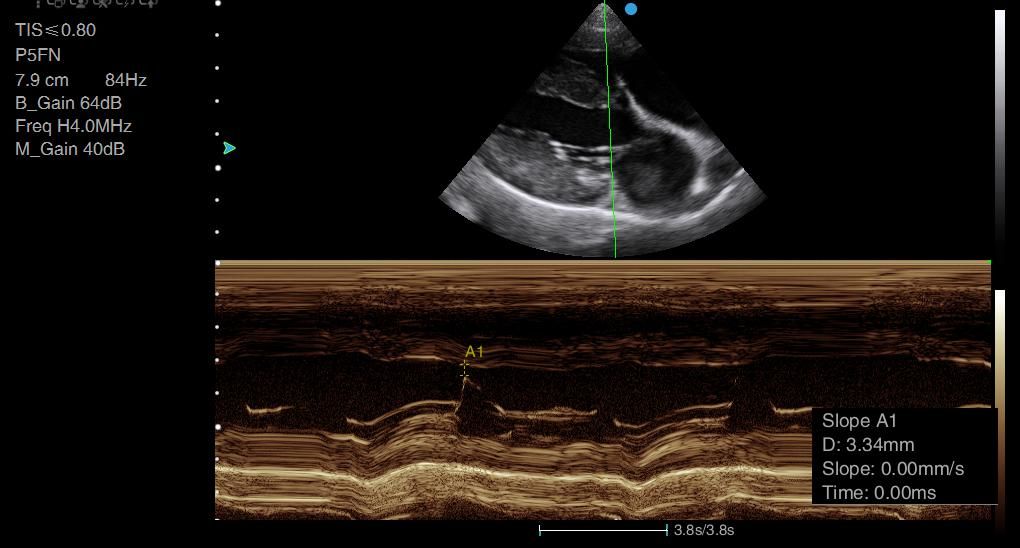

I think the image quality is great and what this machine really excels at is colour, Doppler.

Many machines I've tried the cardiac Doppler functions are just not up to scratch - it is really difficult to assess for turbulence, for example around mitral valves, but also in the abdomen because some machines just slow the frame rate so much that it's impossible to use colour Doppler effectively.

The Apogee 2300V absolutely excels and has really great resolution on its colour Doppler. So if you're interested in cardiac scanning, this is a really good machine to go for.

Images from the Apogee 2300V